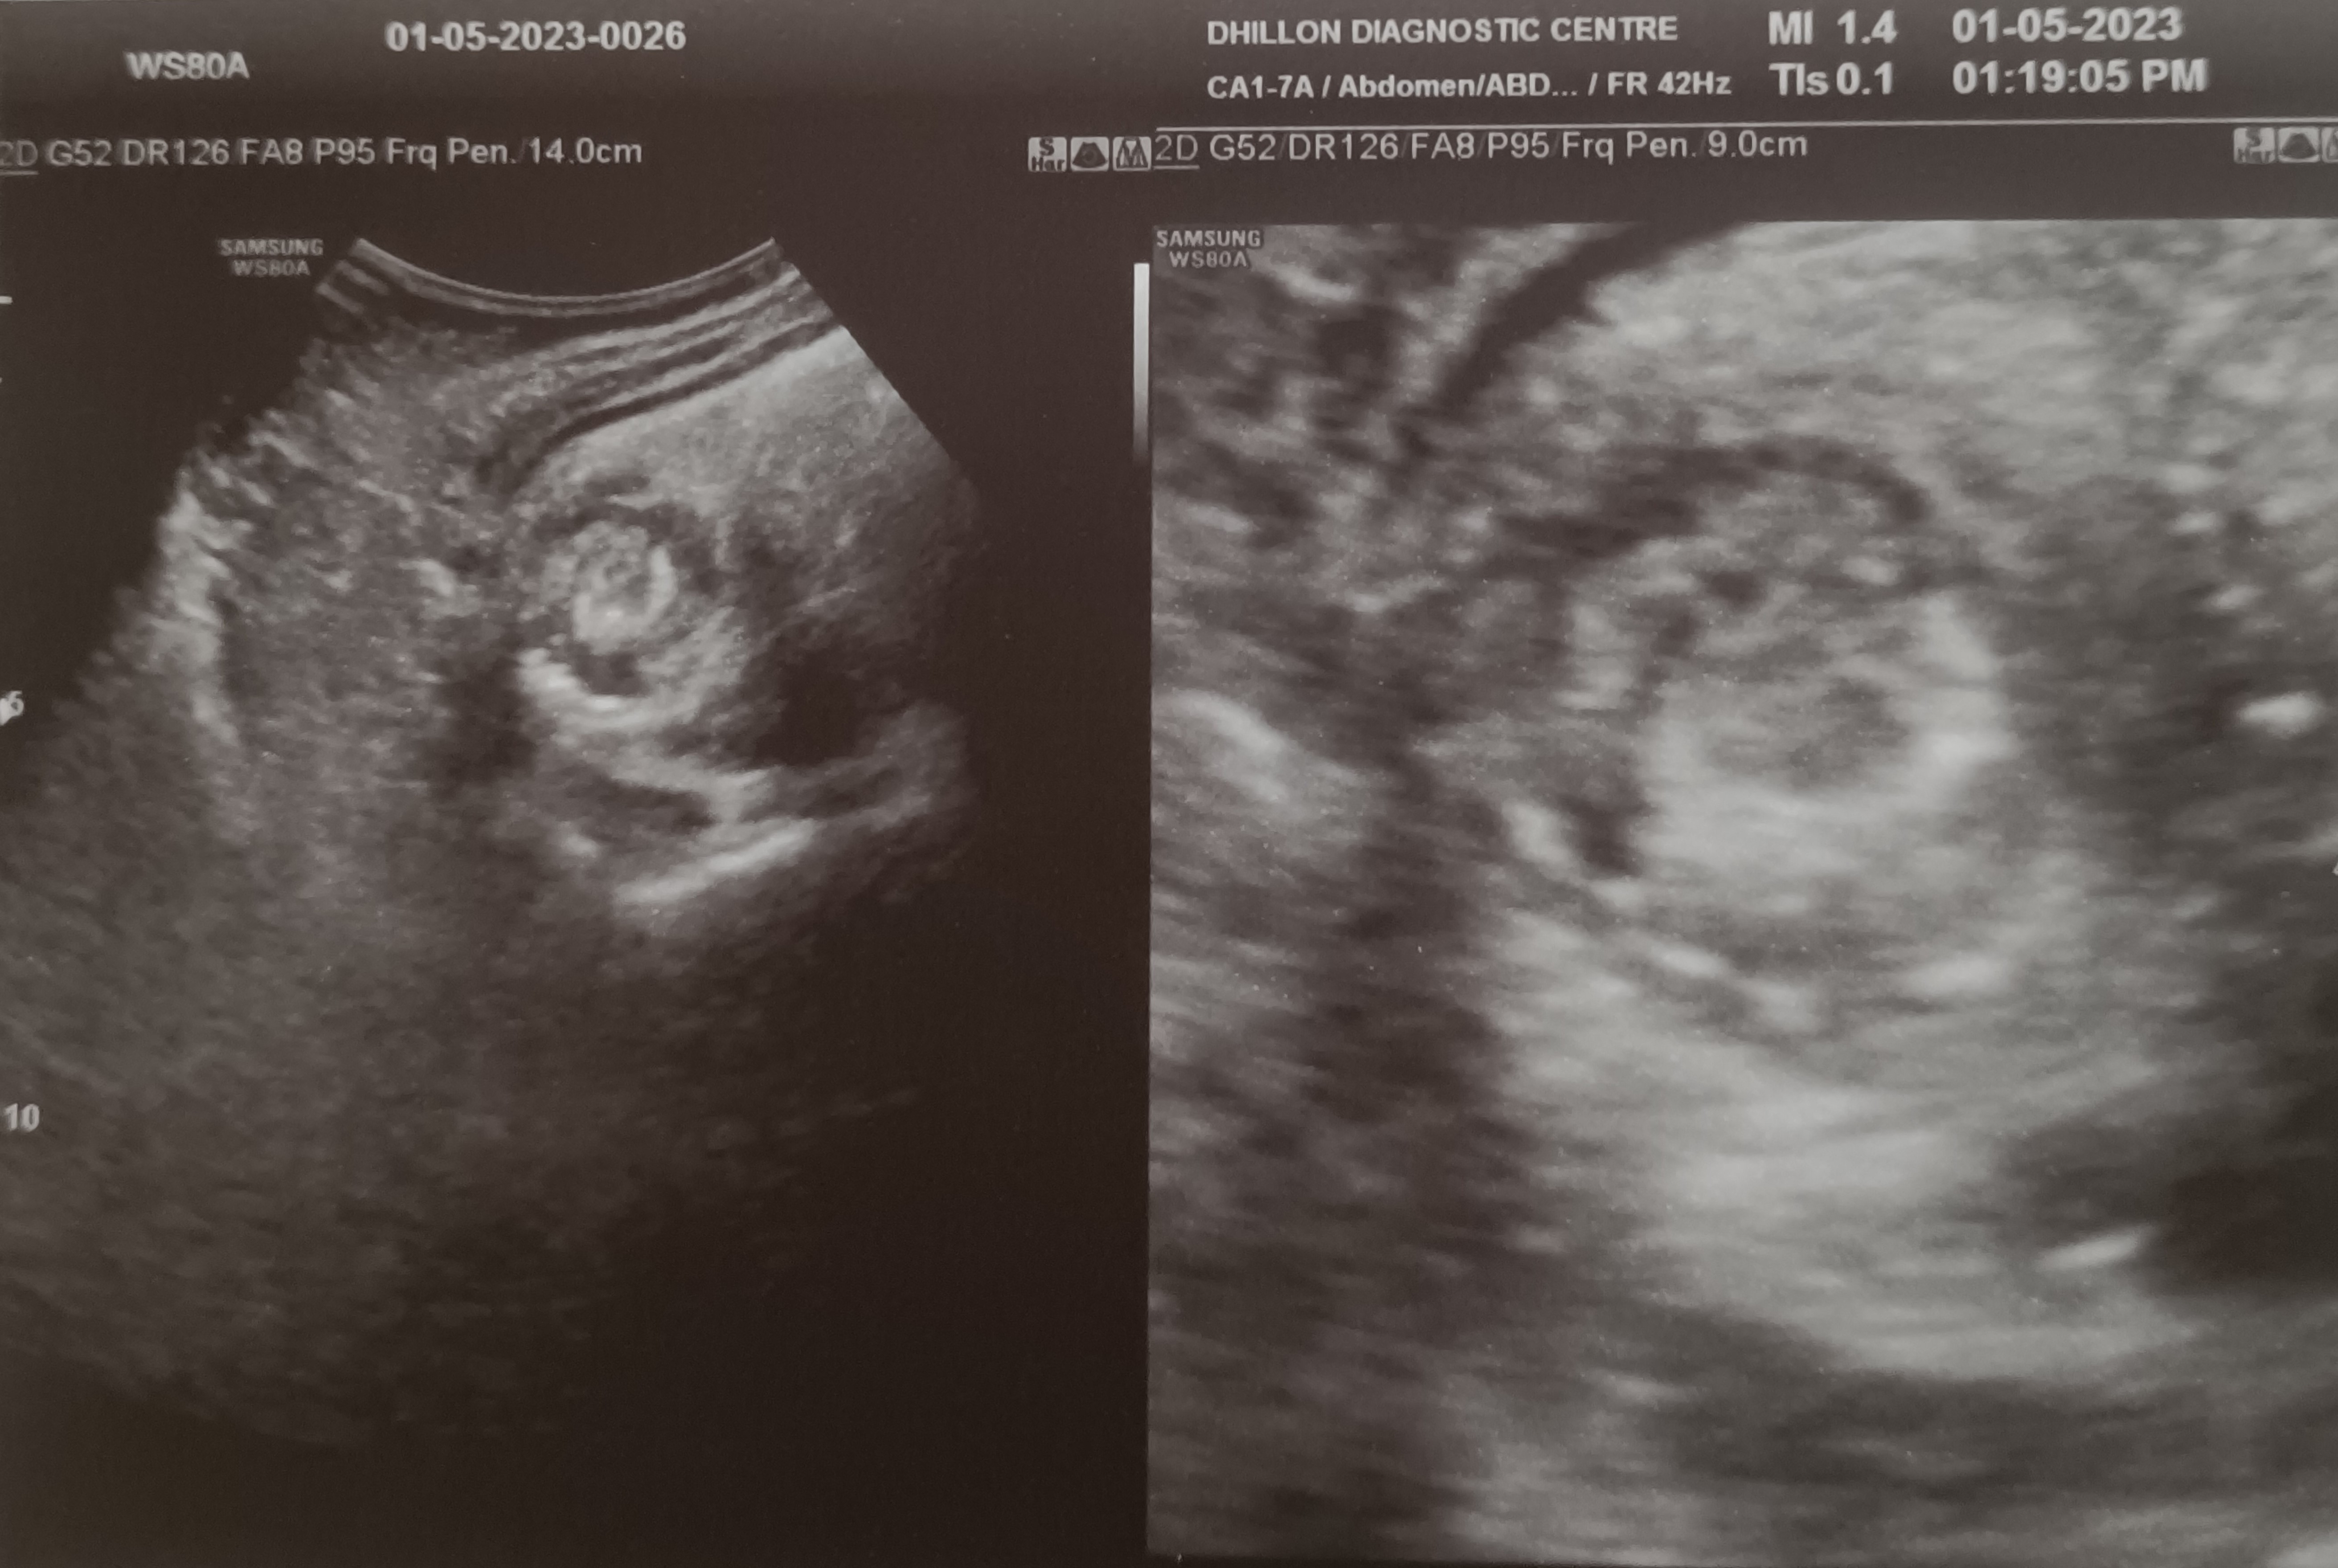

A 7 years old male child admitted with acute abdominal pain showed classic signs of target sign/doughnut sign/pseudo-kidney signs on ultrasound and a mass effect in right iliac fossa on CT. However, the child’s condition improved rapidly and in a few hours he became clinically better and pain free, suggesting spontaneous reduction of the intussusception. Recovered completely on conservative treatment and was not operated.